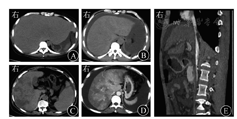

典型CT表现包括[24,25,26,49,50,51]:①肝脏弥漫性肿大,平扫显示肝实质密度不均匀减低;②静脉期和平衡期肝实质呈特征性"地图状""花斑样"不均匀强化,门静脉周围出现的低密度水肿带称为"晕征";③尾状叶、肝左外叶受累稍轻,肝静脉周围肝实质强化程度较高,呈现特征性"三叶草征",肝静脉管腔狭窄或显示不清,下腔静脉肝段受压变细;④通常合并腹水、胸腔积液、胆囊壁水肿和胃肠壁水肿等肝外征象(图3)。急性期患者较少合并脾大、食管胃静脉曲张等征象。